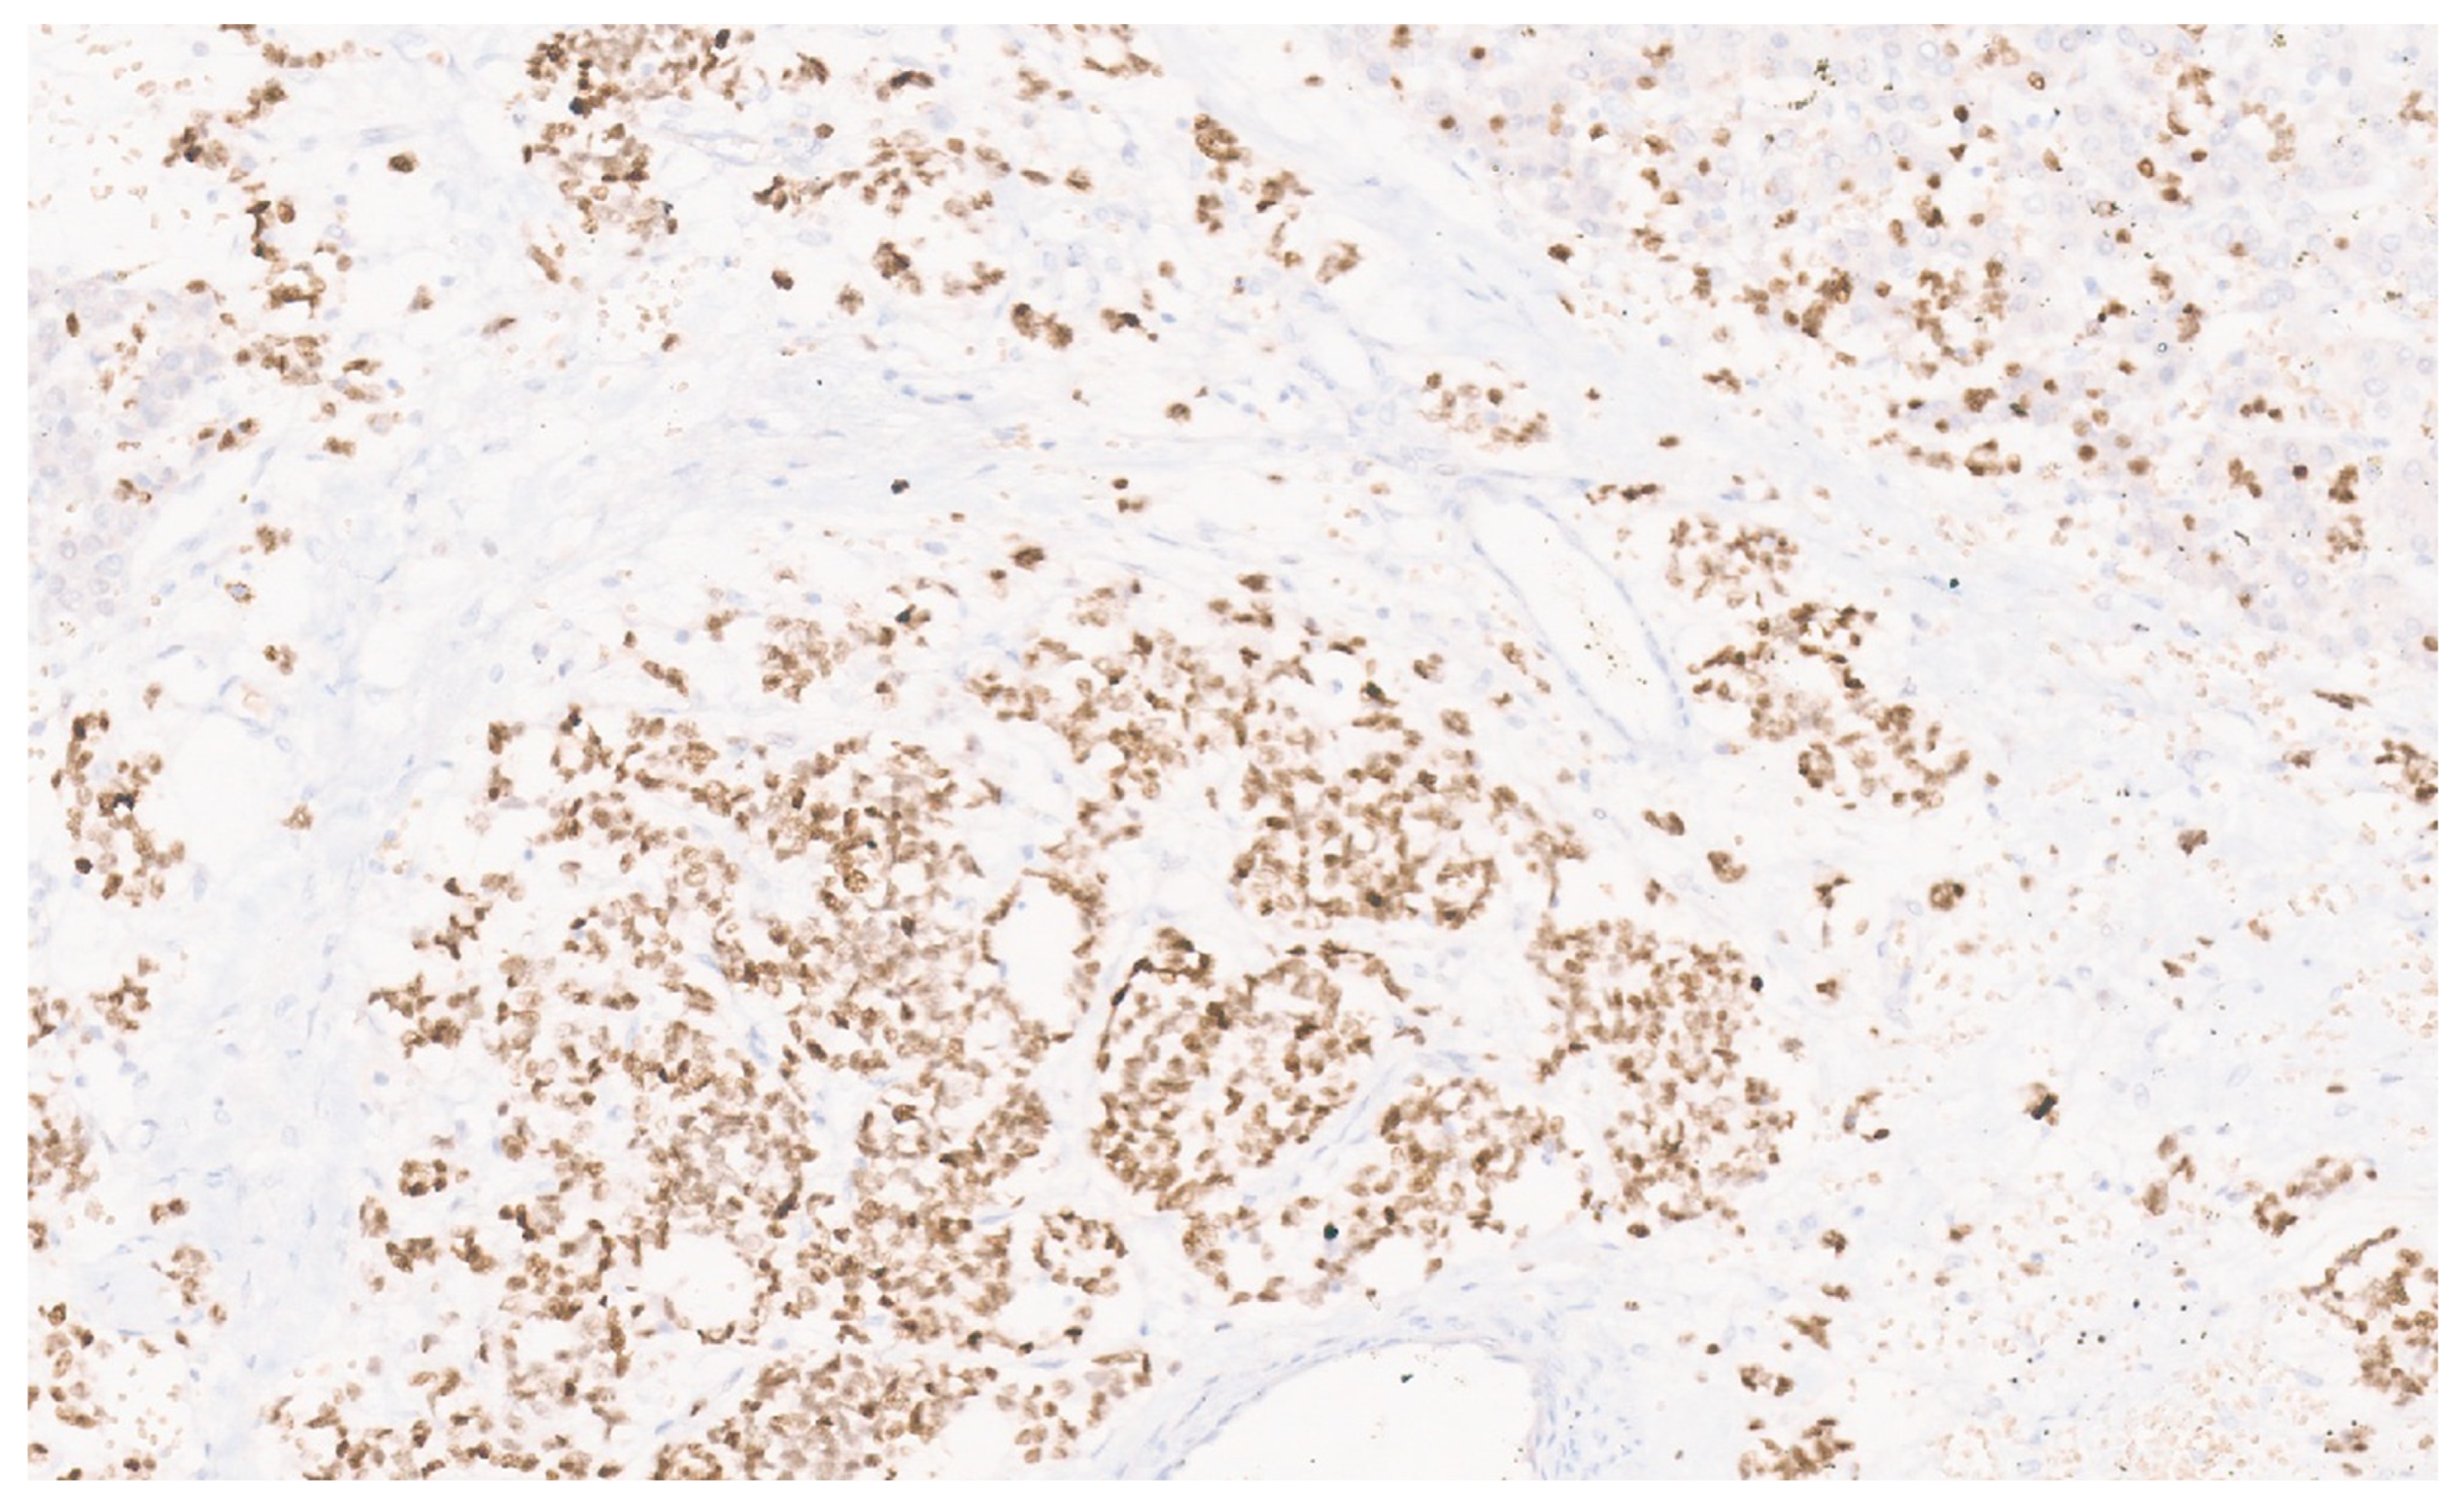

9.3. Pathology